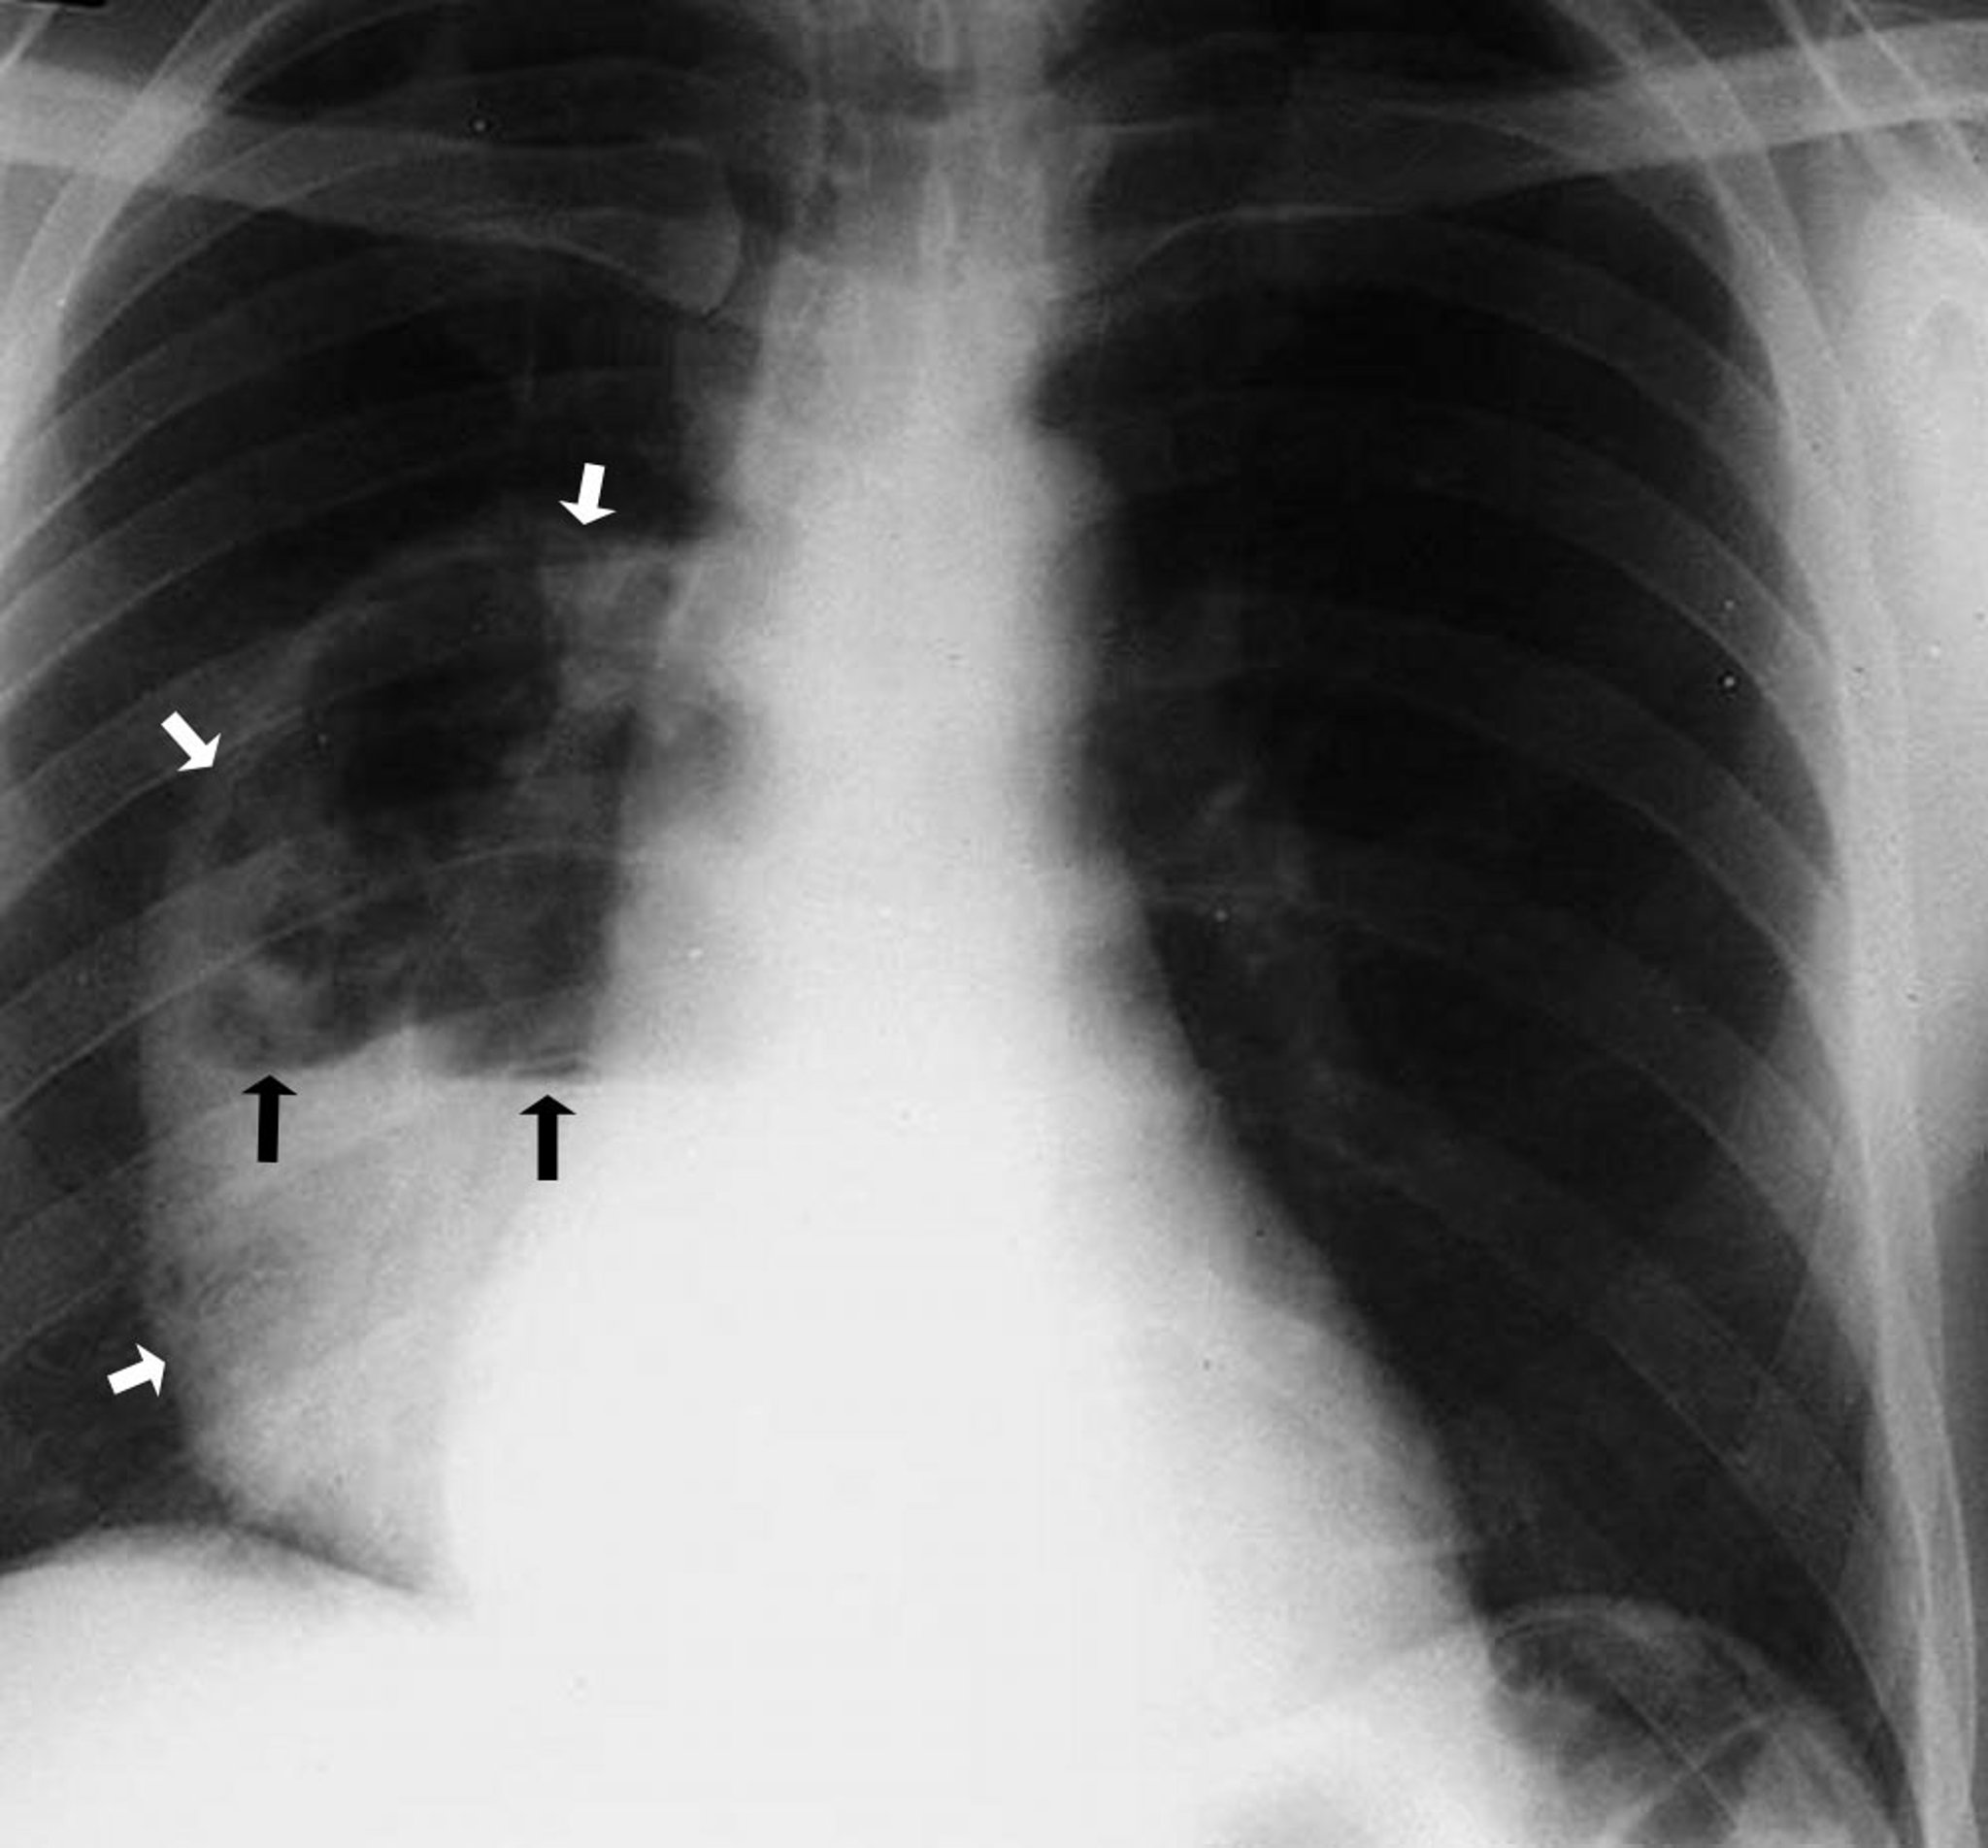

Абсцес легень (рентгенограма)

This photo shows a large right lower lobe abscess demonstrating a cavity that contains an air-fluid level. The white arrows point out the boundary of the abscess showing the walls separated from the lung parenchyma. The black arrows demarcate the level where the air above and fluid below meet.

By permission of the publisher. From Leaf H. In Atlas of Infectious Diseases: Pleuropulmonary and Bronchial Infections. Edited by GL Mandell (series editor) and MS Simberkoff. Philadelphia, Current Medicine, 1996.